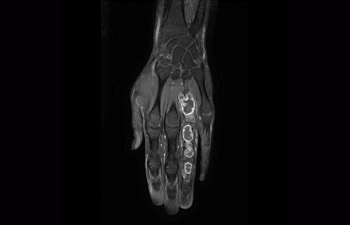

Tumor en mano/muñeca